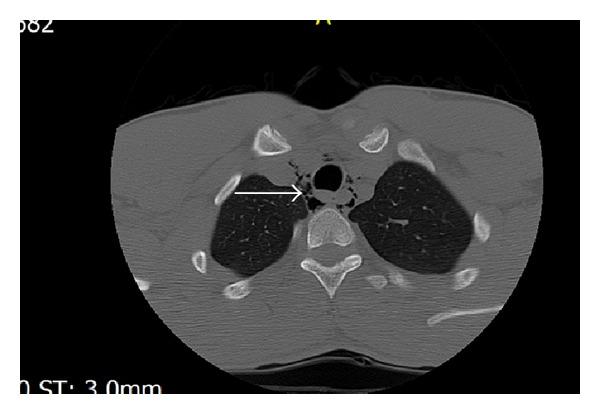

Spontaneous pneumomediastinum is an unusual and benign condition in which air is present in mediastinum. A 20-year-old male patient presented to ED with complaint of hoarseness and odynophagia from the day before, after weightlifting. The patient was nonsmoker and denied history of other diseases. On physical examination he had no dyspnea with normal vital signs. Throat examination and pulmonary auscultation were normal and no crepitation was palpable. We could not find subcutaneous emphysema in neck and chest examination. In neck and chest X-ray we found that air is present around the trachea. There was no apparent pneumothorax in CXR. In cervical and chest CT free air was present around trachea and in mediastinum. Subcutaneous emphysema was also evident. But there was no pneumothorax. The patient was admitted and went under close observation, oxygen therapy, and analgesic. The pneumomediastinum and subcutaneous emphysema gradually resolved within a week by conservative therapy and he was discharged without any complication. Many different conditions could be trigged because of pneumomediastinum but it is rarely seen in intense physical exertion such as weightlifting and bodybuilding. Two most common symptoms are retrosternal chest pain and dyspnea. But the patient here complained of hoarseness and odynophagia.

自发性纵隔气肿是一种罕见的良性病症,纵隔内存在气体。一名20岁男性患者因前一天举重后出现声音嘶哑和吞咽痛而就诊于急诊科。该患者不吸烟,否认有其他疾病史。体格检查时,他生命体征正常,无呼吸困难。咽喉检查和肺部听诊正常,未触及捻发音。在颈部和胸部检查中未发现皮下气肿。在颈部和胸部X线检查中,我们发现气管周围有气体。胸部X线片未见明显气胸。颈部和胸部CT显示气管周围及纵隔内有游离气体。皮下气肿也很明显。但无气胸。患者入院并接受密切观察、氧疗和镇痛治疗。通过保守治疗,纵隔气肿和皮下气肿在一周内逐渐消退,患者出院时无任何并发症。纵隔气肿可能引发许多不同情况,但在举重和健美等剧烈体力活动中很少见。最常见的两种症状是胸骨后胸痛和呼吸困难。但该患者主诉为声音嘶哑和吞咽痛。